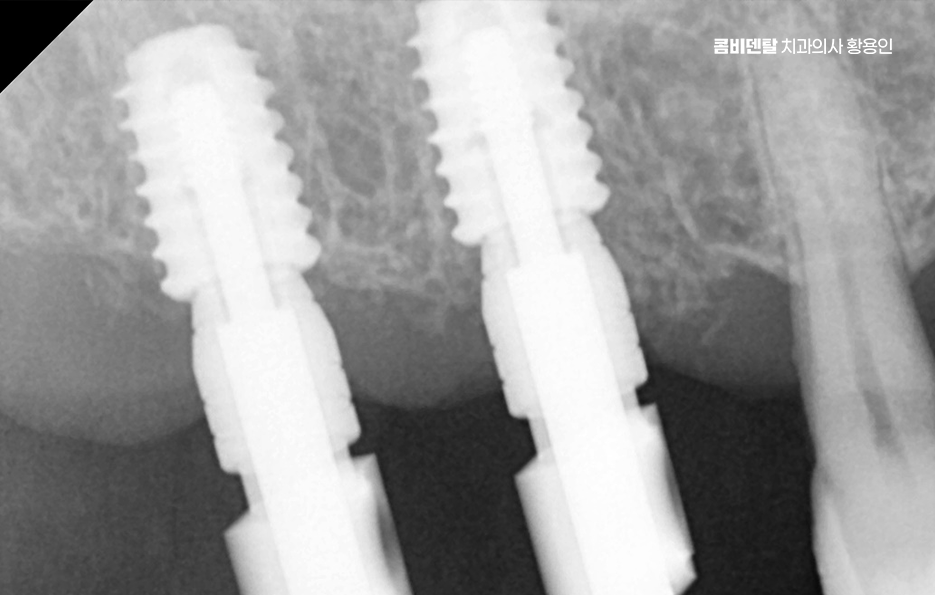

임플란트는 턱뼈 안에 임플란트의 고정체(인공치근)를 식립해서 치아를 대신하는 구조로 이 고정체가 제대로 자리를 잡고 버텨주려면 최소한의 잇몸뼈 높이와 넓이, 골질이 확보돼 있어야 안정성이 확보되는 거예요. 그런데 이 뼈가 부족한 상태에서 임플란트 뼈이식 안하면 그리고 억지로 임플란트를 심게 되면 어떤 일이 생기냐면, 첫째로 임플란트가 제대로 뼈와 붙지 못해서 탈락하거나 흔들릴 가능성이 높고 둘째로는 식립 부위 주변의 잇몸이 꺼지면서 심미적으로도 부자연스러운 결과를 낳을 수 있어요

잇몸뼈는 자연치아를 잃고 나면 시간이 지남에 따라 서서히 흡수되는데 특히 상실한 치아를 오랫동안 방치한 경우에는 뼈가 눈에 띄게 줄어드는 일이 흔하고, 치주염이나 염증이 반복된 경우에도 주변 골조직이 녹아내려 뼈의 두께와 높이가 부족해지게 되는데 이런 상태에서 임플란트 뼈이식 안하면 그리고 임플란트를 바로 심는다면, 뼈의 지지력이 부족하기 때문에 인공치근이 쉽게 움직이거나 주변에 염증이 생겨 골융합이 제대로 되지 않게 되고 결국엔 수개월 후에 탈락하거나 실패하게 되는 일이 생길 수 있는 거예요.

실제로 초기에는 잘 버티는 듯 보여도 시간이 지나면서 점점 임플란트 주변의 골이 소실되고, 결국엔 고정체가 노출되면서 통증, 염증, 보철물 탈락 같은 문제가 연쇄적으로 이어질 수 있어요

그렇다면 뼈이식을 언제, 어떻게 계획해야 하는지가 중요한데 첫 번째는 임플란트 식립 전 단계에서 충분한 영상 진단과 분석을 통해 뼈의 양과 질을 정밀하게 평가해야 하며 단순 파노라마 X-ray만으로는 확인이 어려운 입체적인 골량이나 신경과의 거리, 부비동 위치 등을 정확히 파악하려면 3D CT 촬영이 필수적이고 이를 통해 상악동 거상술이 필요한지 등을 판단할 수 있어요.